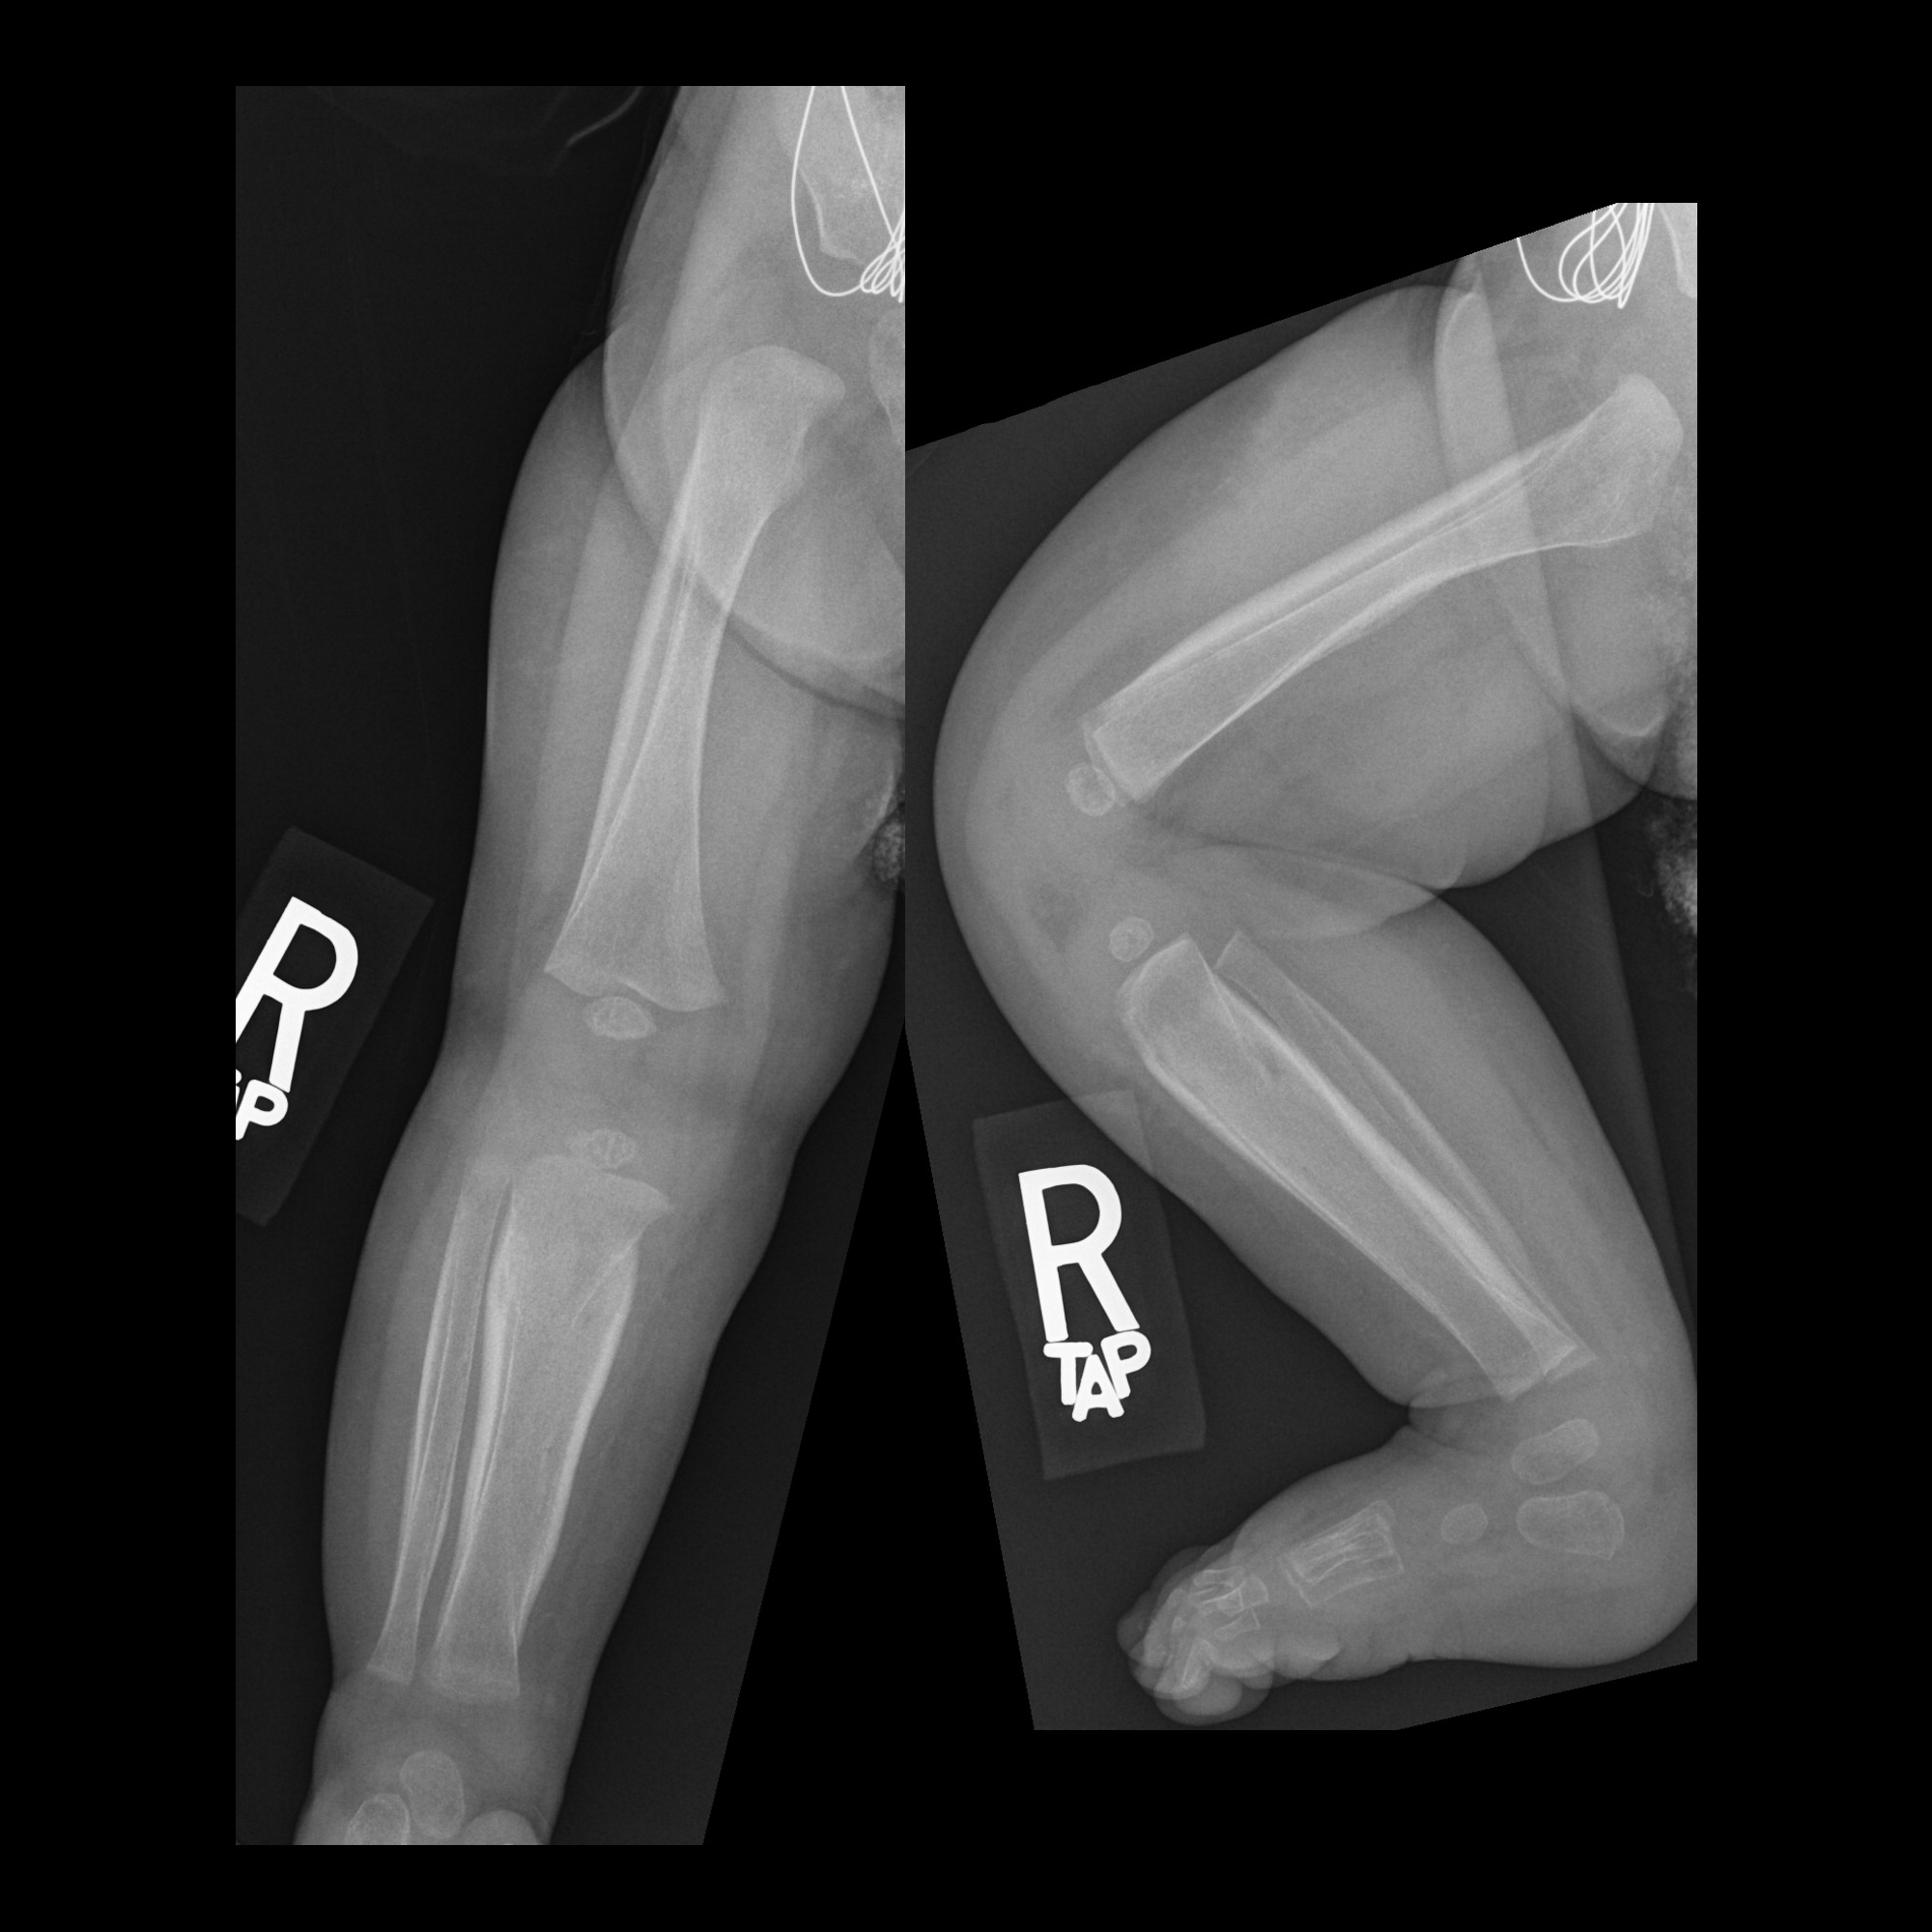

Congenital Amputee